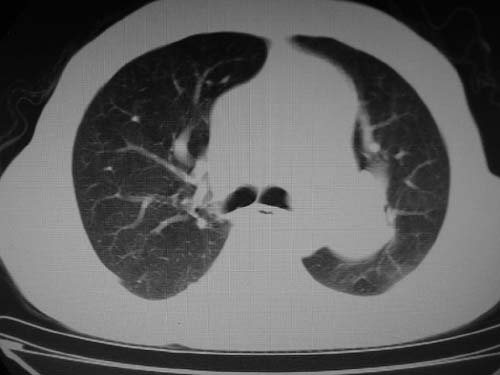

左肺动脉异常增粗,建议ct增强,排除肺门肿瘤

右肺上叶继发性肺结核。

右侧胸膜增厚、钙化,左侧胸膜反应

右肺上叶尖段结核;左肺下叶占位?建议增强扫描。右侧胸膜增厚;右肺局限性肺气肿。